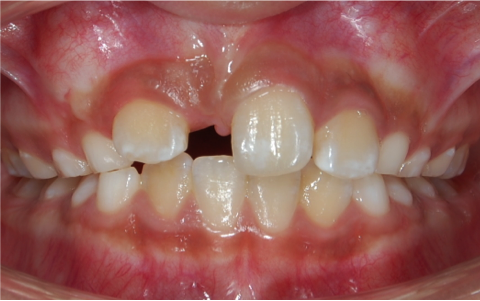

Traccion de un diente retenido

Antes